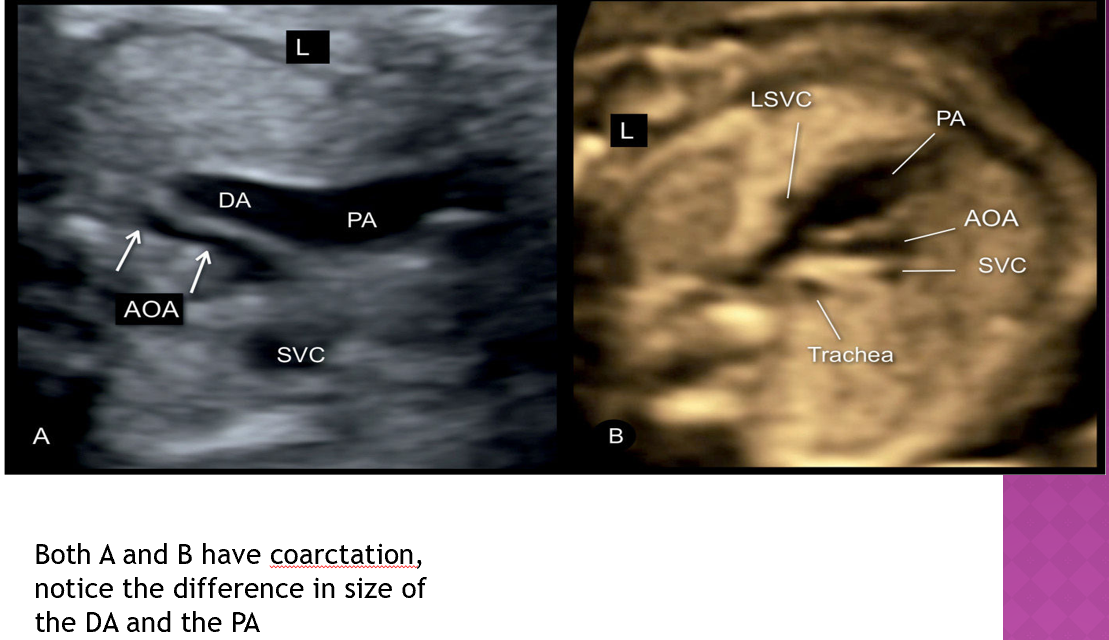

compare size of pa and ao in utero

they should be relatively the same size

recognize

coarctation of the ao is highly associated with

VSD, PDA, bicsupid ao valve

coarctation is associated with

bicuspid ao valve (46%)

PDA

abn of subclavian art